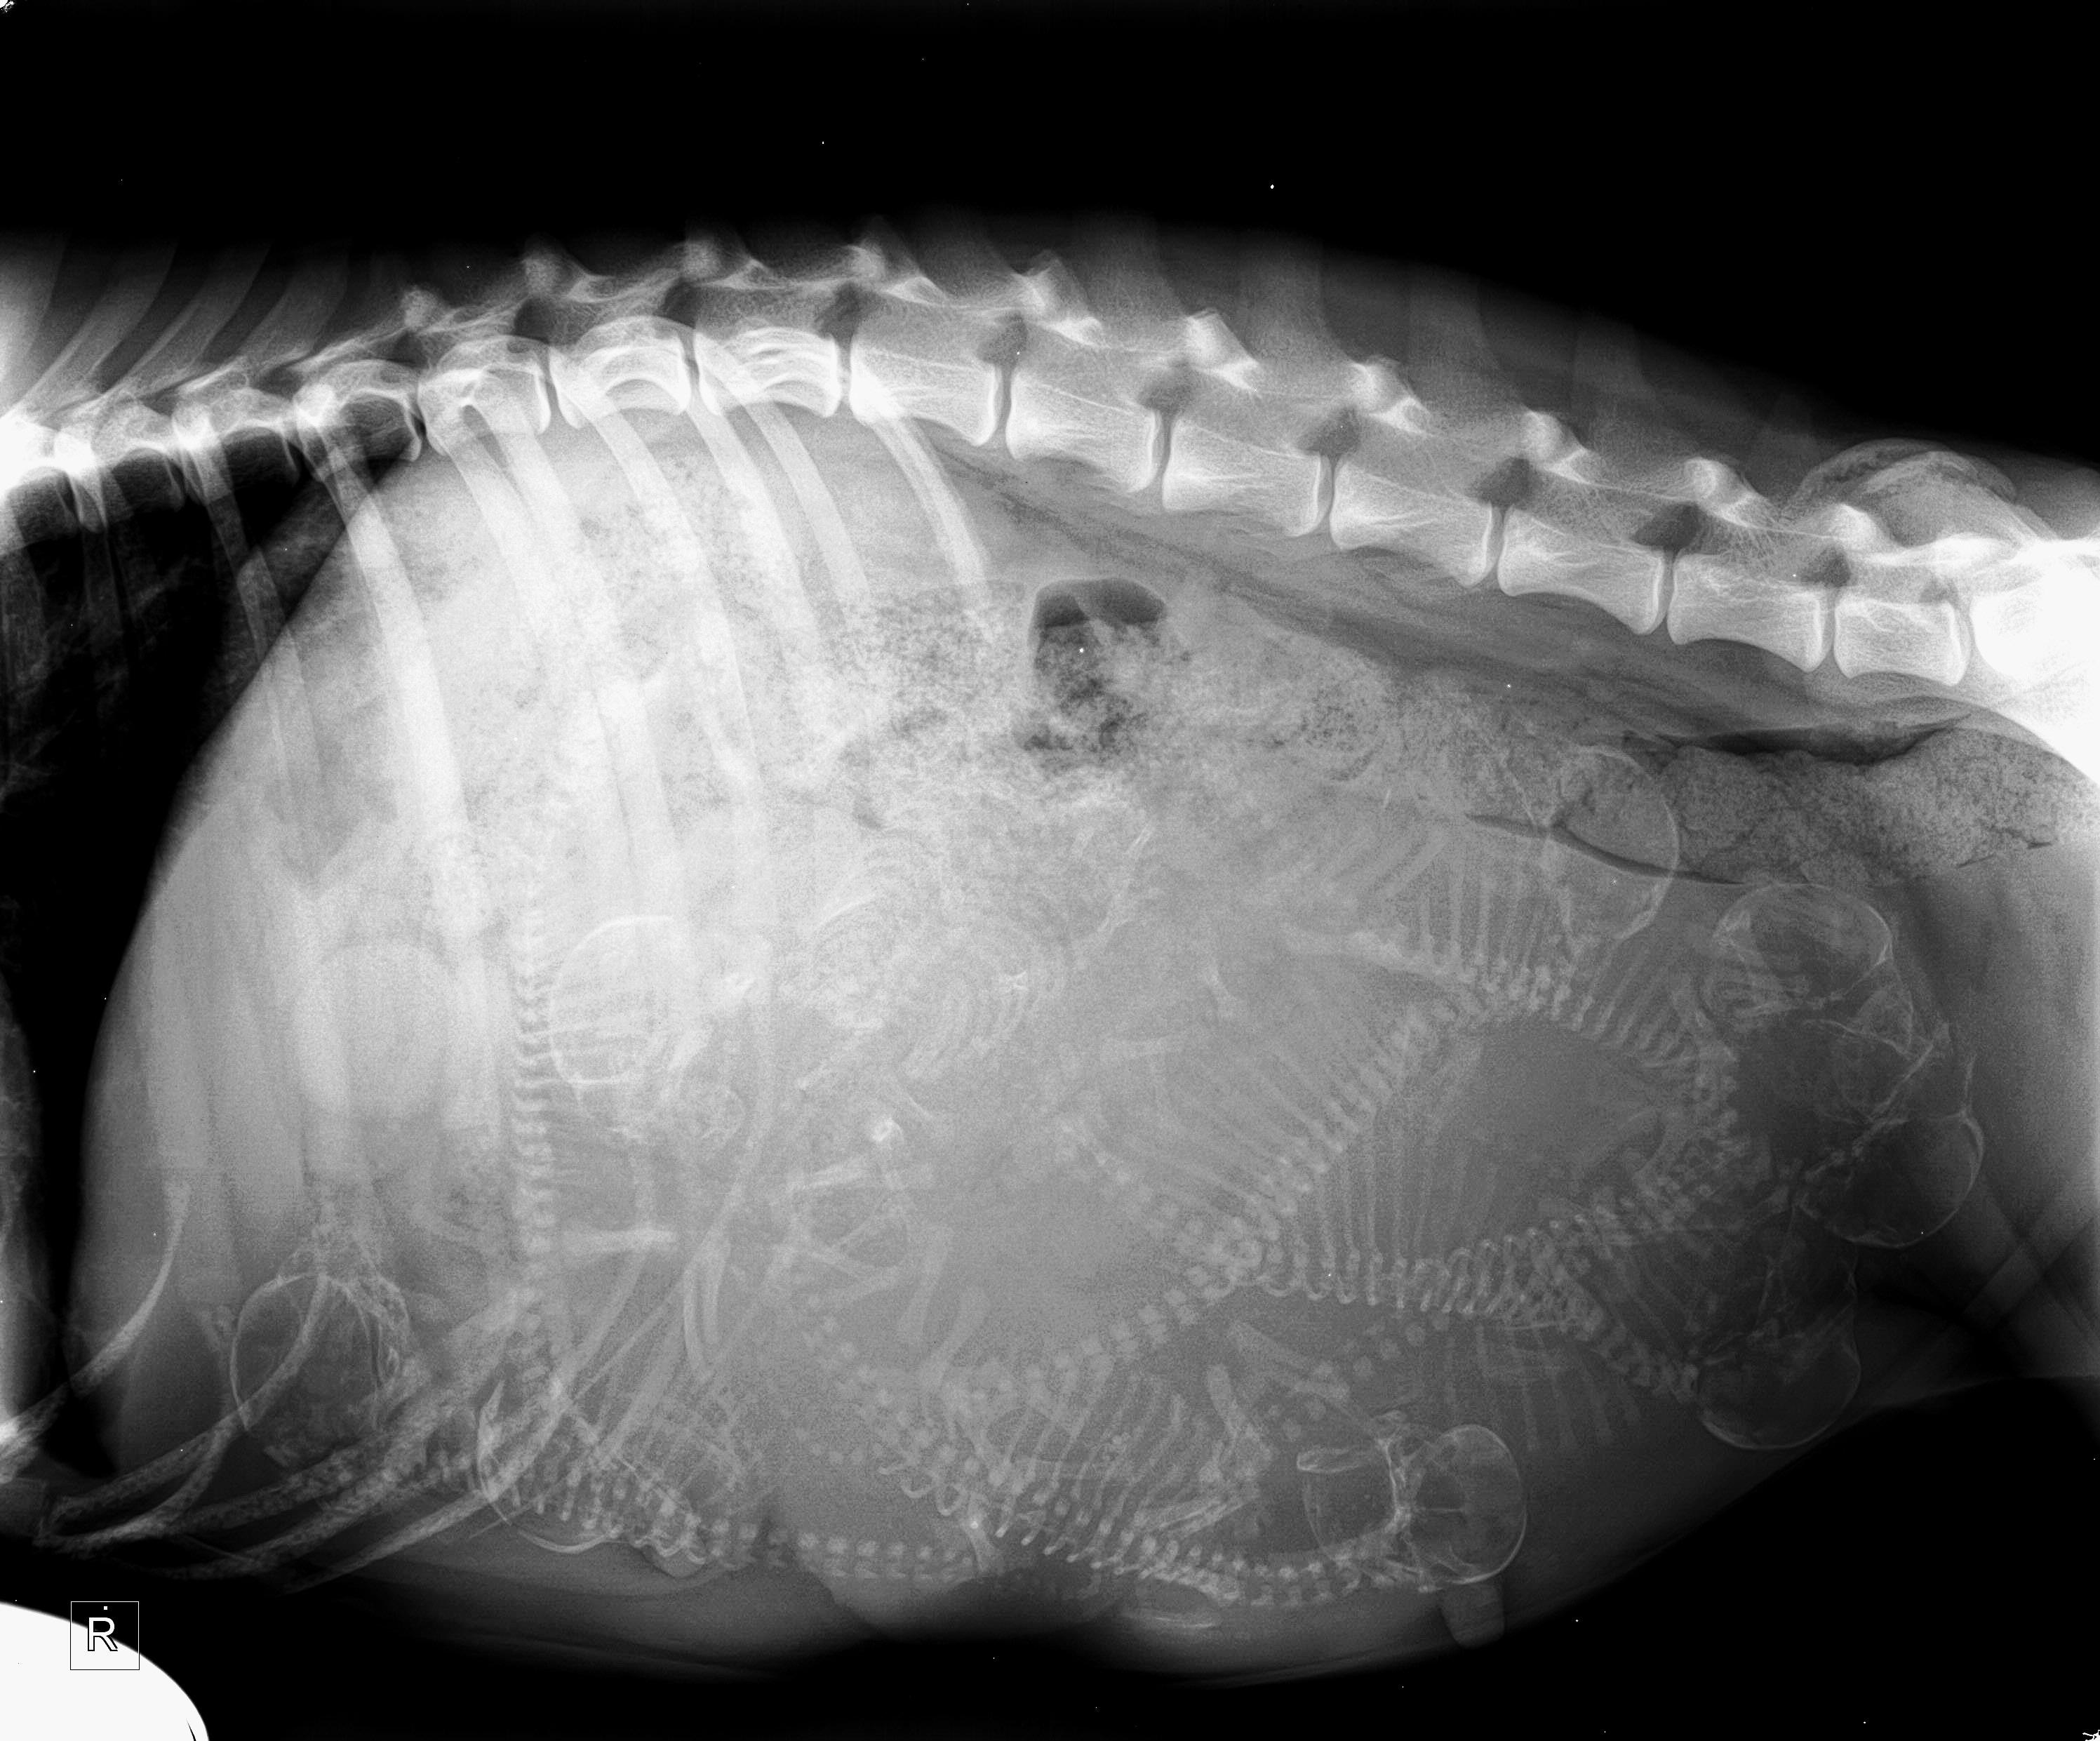

Pregnant Dog Counting Pups Xray YouTube How Much Is A Dog Pregnancy X Ray Obviously, all three methods must be made by a qualified veterinary to avoid, in the best of. The general belief is that it's safe after. Around week 4, you will start to notice that dog's belly swells. Bloodwork can be used as a health check and to confirm pregnancy. However, the cost can vary. Here are cost estimates for things. How Much Is A Dog Pregnancy X Ray.

Xray Pregnant Dog Show 7 Fetuses Foto de stock 1262090236 Shutterstock How Much Is A Dog Pregnancy X Ray Obviously, all three methods must be made by a qualified veterinary to avoid, in the best of. Dogs are pregnant for between 63 to 67 days, which is more or less 9 weeks. However, the cost can vary. There are three main methods for diagnosing pregnancy in dogs: Here are cost estimates for things that your vet might do if. How Much Is A Dog Pregnancy X Ray.